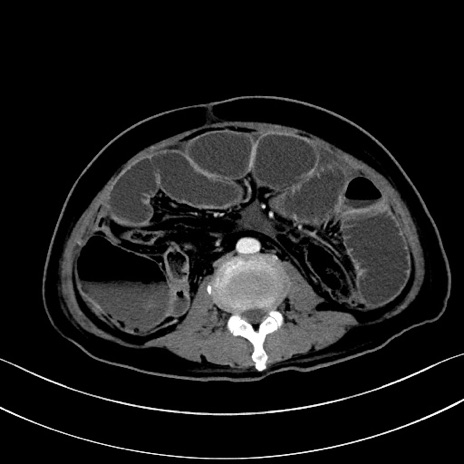

冠状断像